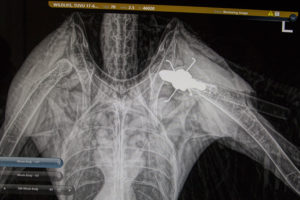

Nasty looking apparatus

September 11, 2017/by Terry Stevens